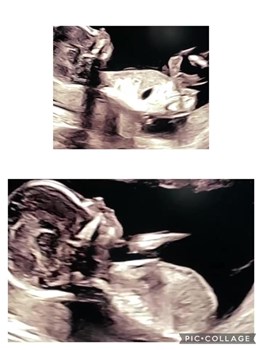

Se hele opslaget på RR Fliserens’ FacebooksideSe lige denne søde lille pige 😍 hun er 15 uger. Vejer kun 125 gram, men hun er næsten færdig i sin udvikling af organer, og her øver hun sin vejrtrækning og drikker fostervand. Hun er et lille mirak...

Se hele opslaget på Hjertelyd - scanningsklinik for gravides Facebookside